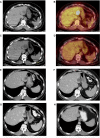

Ipilimumab improves survival in advanced melanoma and can induce immune-mediated tumor vasculopathy. Besides promoting angiogenesis, vascular endothelial growth factor (VEGF) suppresses dendritic cell maturation and modulates lymphocyte endothelial trafficking. This study investigated the combination of CTLA4 blockade with ipilimumab and VEGF inhibition with bevacizumab. Patients with metastatic melanoma were treated in four dosing cohorts of ipilimumab (3 or 10 mg/kg) with four doses at 3-week intervals and then every 12 weeks, and bevacizumab (7. 5 or 15 mg/kg) every 3 weeks. Forty-six patients were treated. Inflammatory events included giant cell arteritis (n = 1), hepatitis (n = 2), and uveitis (n = 2) VSports手机版. On-treatment tumor biopsies revealed activated vessel endothelium with extensive CD8(+) and macrophage cell infiltration. Peripheral blood analyses demonstrated increases in CCR7(+/-)/CD45RO(+) cells and anti-galectin antibodies. Best overall response included 8 partial responses, 22 instances of stable disease, and a disease-control rate of 67. 4%. Median survival was 25. 1 months. Bevacizumab influences changes in tumor vasculature and immune responses with ipilimumab administration. The combination of bevacizumab and ipilimumab can be safely administered and reveals VEGF-A blockade influences on inflammation, lymphocyte trafficking, and immune regulation. These findings provide a basis for further investigating the dual roles of angiogenic factors in blood vessel formation and immune regulation, as well as future combinations of antiangiogenesis agents and immune checkpoint blockade. .